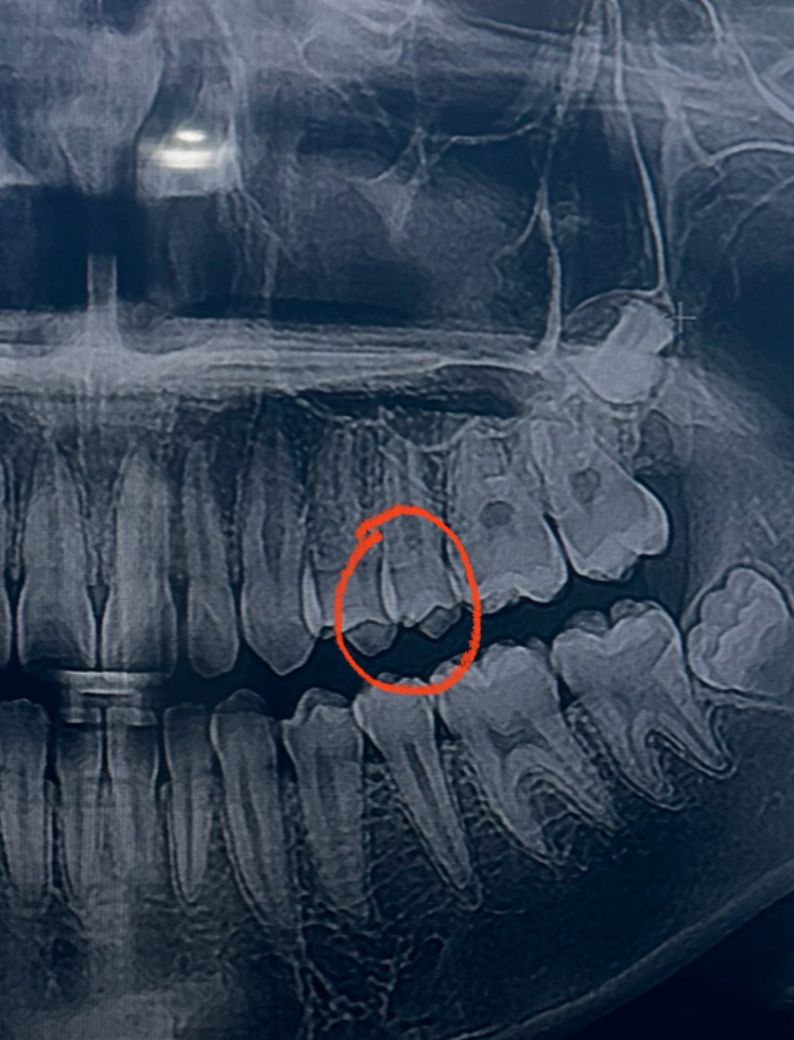

25~26 치아고 첫번째, 세번째 사진이 최근 두번째 사진이 올해 2월 입니다 인접면 충치가 맞는지 얼마나 진행되었는지 궁금합니다

• 1번 째 사진

엑스레이 상에서 명확히 관찰되지는 않는 것으로 보이며 관리 하면서 지켜봐도 될 것 같습니다.

엑스레이 상으로는 인접면 충치가 심해 보이진 않으니 일단은 관리를 해서 사용해보셔도 될것같습니다.

25~26 치아고 첫번째, 세번째 사진이 최근 두번째 사진이 올해 2월 입니다 인접면 충치가 맞는지 얼마나 진행되었는지 궁금합니다 -> 25,26 사이 인접면 충치 크게 문제 없어 보입니다

사진으로 봤을 경우에는 인접면에 어두운 면이 보입니다. 충칠 가능성이 높지만 정확한 확인은 육안으로 확인을 해봐야 알 수 있을것으로 생각됩니다.

자세한 확인을 위해서 치과에서 진료를 받아보는 것을 권유드립니다.